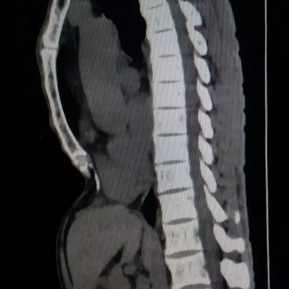

The anterior chest wall exhibits an obvious depression, causing severe compression and displacement of the heart to the left thoracic cavity. The Haller index is notably high at 5.6.

During the surgery, a 2 cm incision was made on each side of the chest wall, followed by a third 2 cm incision below the xiphoid process. After thorough pre-shaping of the bone structure at the depression, two bars were inserted to correct the deformity. After the surgery, the deformity was completely resolved, and the chest wall returned to its normal appearance.